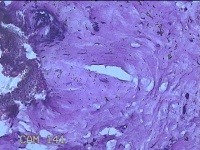

性别

女

年龄

27岁

临床诊断

乳腺脓肿

一般病史

发现右侧乳腺脓肿1个月余,伴局部疼痛不适。

标本名称

右侧乳头下方结节

大体所见

灰白暗红色结节0.8x0.5x0.3cm一个,表面糜烂。

图2

组织没固定好